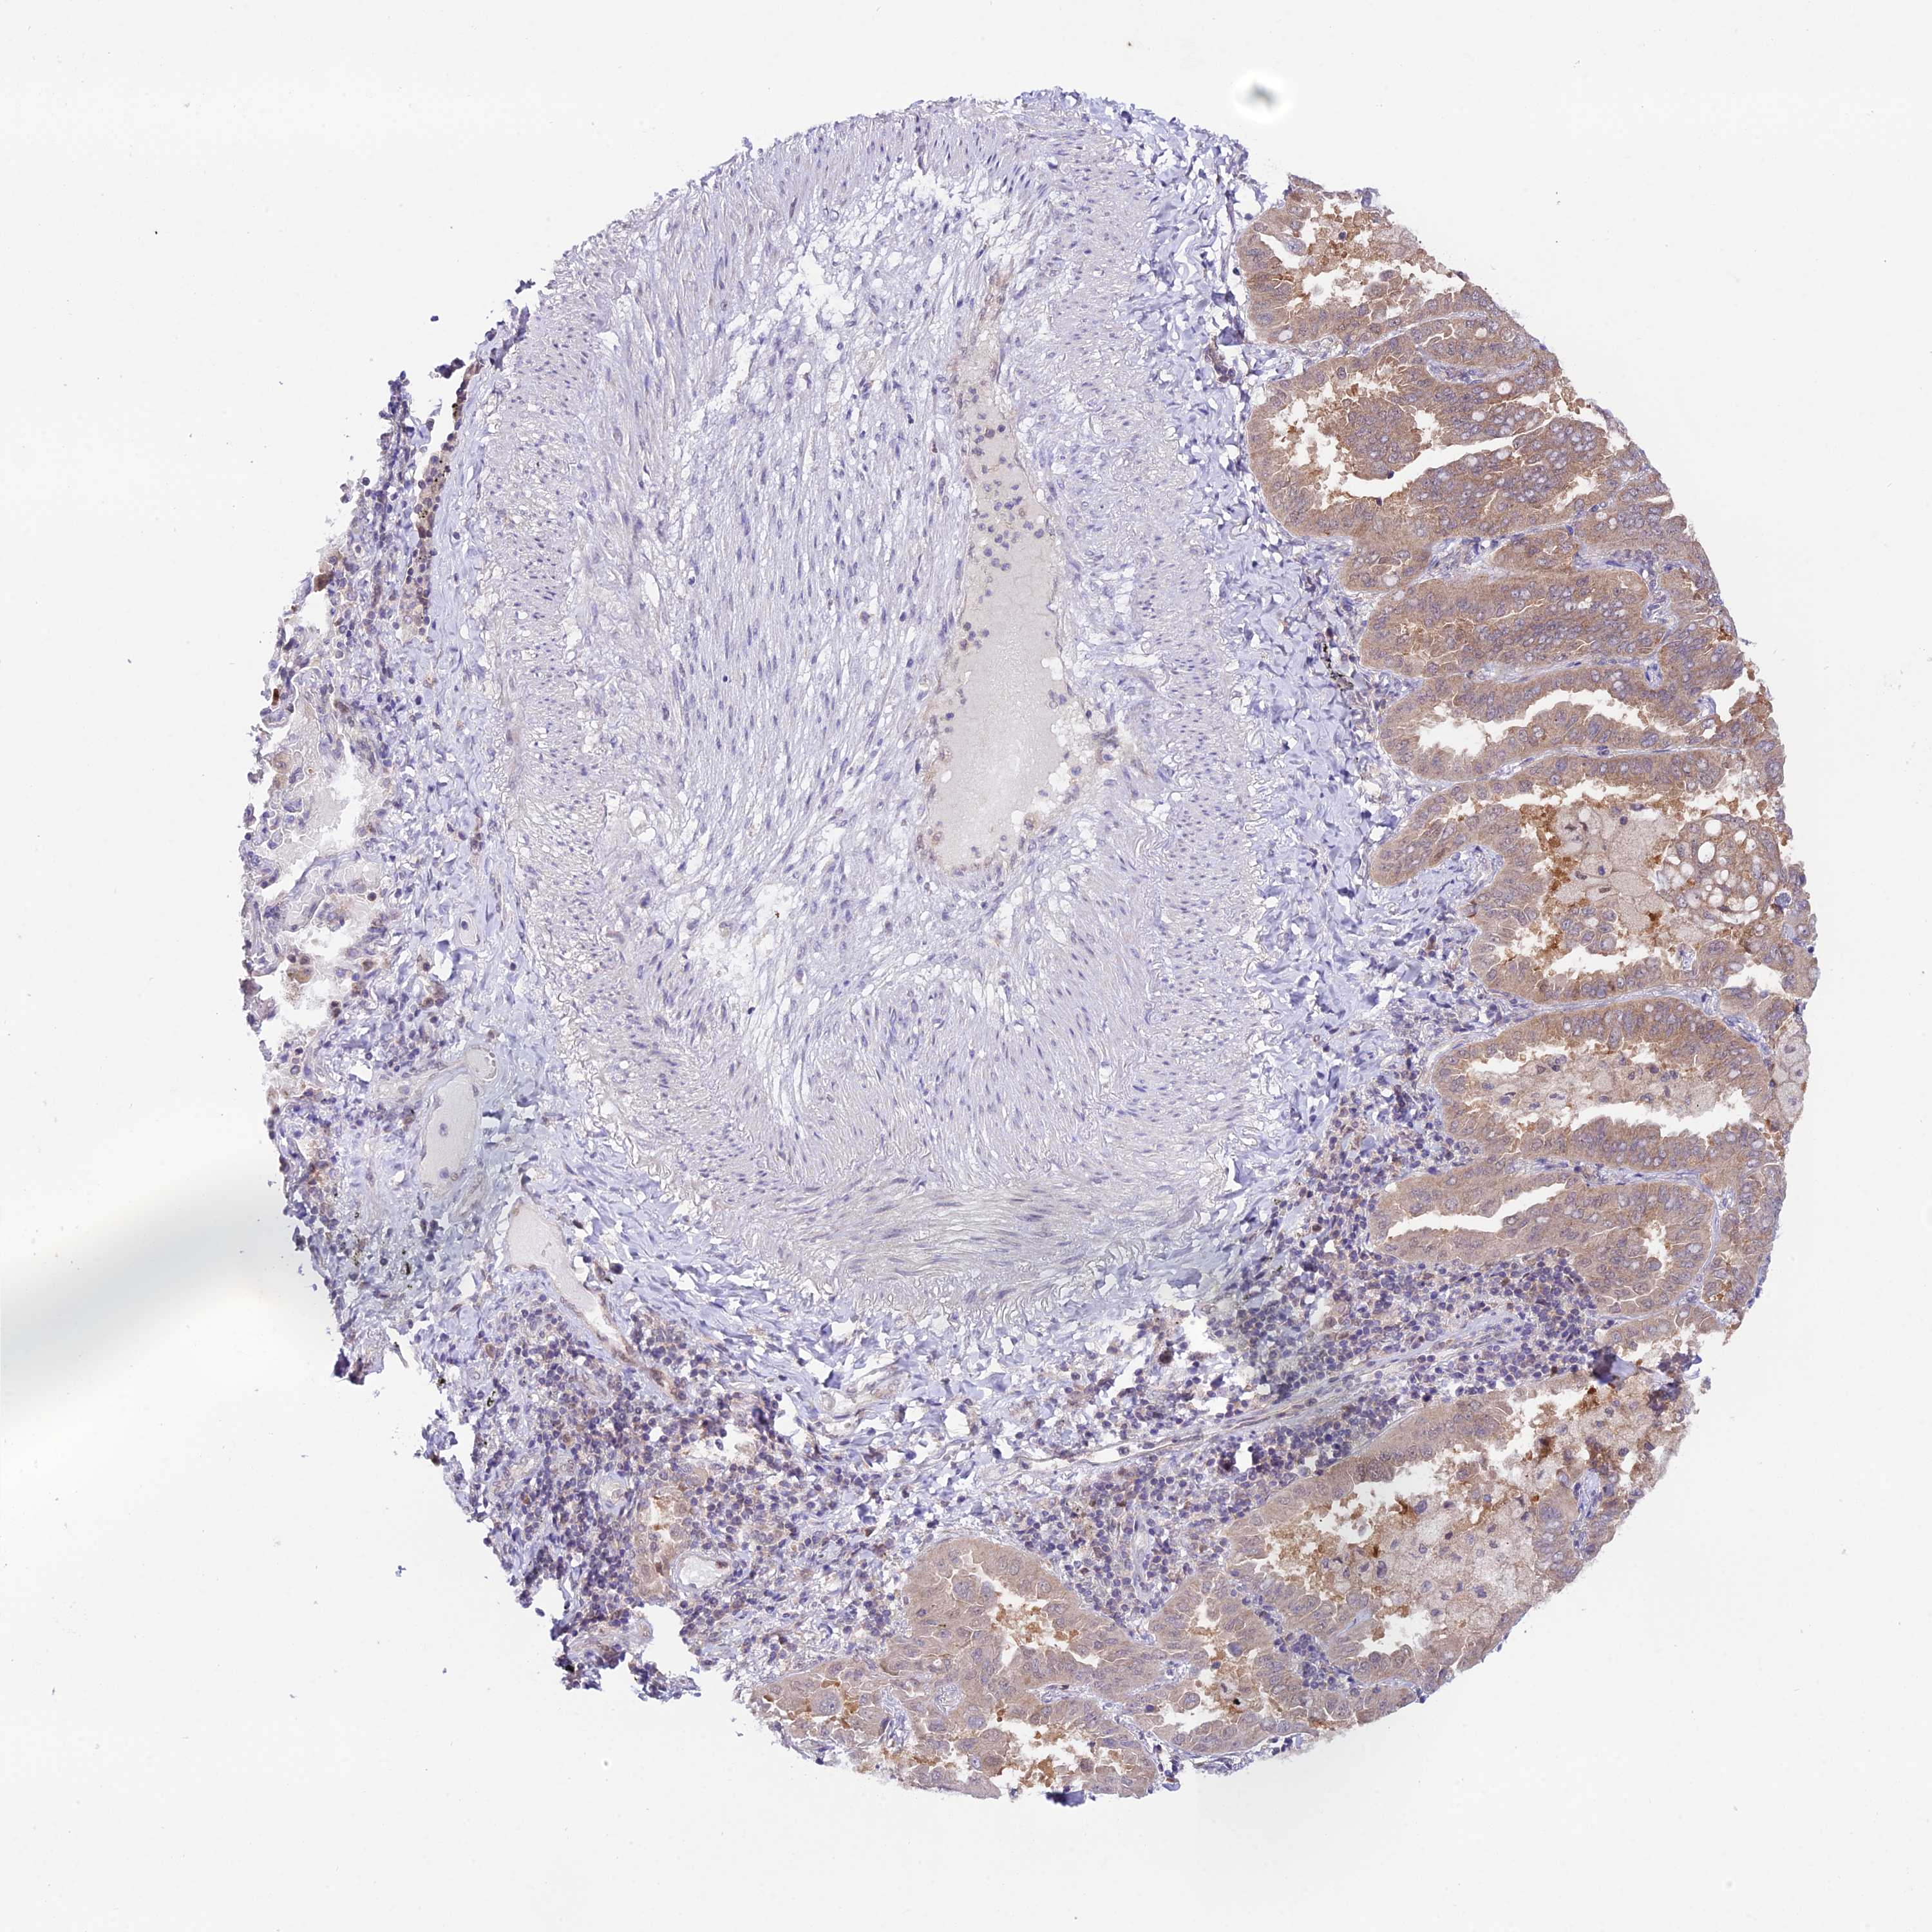

LUNG ADENOCARCINOMA (VALIDATION) - Interactive survival scatter ploti

The Survival Scatter plot shows the clinical status (i.e. dead or alive) for all individuals in the patient cohort, based on the same data that underlies the corresponding Kaplan-Meier plots. Patients that are alive at last time for follow-up are shown in blue and patients who have died during the study are shown in red.

The x-axis shows the expression levels (FPKM) of the investigated gene in the tumor tissue at the time of diagnosis. The y-axis shows the follow-up time after diagnosis (years). Both axes are complimented with kernel density curves demonstrating the data density over the axes. The top density plot shows the expression levels (FPKM) distribution among dead (red) and alive patients (blue). The right density plot shows the data density of the survived years of dead patients with high and low expression levels respectively, stratified using the cutoff indicated by the vertical dashed line through the Survival Scatter plot. This cutoff is automatically defined based on the FPKM cutoff that minimizes the p-score. The cutoff can be changed by dragging the vertical line or by entering a cutoff value in the square labeled "Current cut-off".

Under the Survival Scatter plot the p-score landscape (black curve; left axis) is shown together with dead median separation (red curve; right axis). Dead median separation is the difference in median mRNA expression between patients who have died with high and low expression, respectively. It is calculated as follows: median FPKM expression of dead patients with high expression - median FPKM expression of dead patients with low expression. This is intended to aid the user in visually exploring custom cutoffs and the associated p-scores and dead median separation.

Individual patient data is displayed and can be filtered by clicking on one or more of the category buttons on the top of the page. Categories describing expression level and patient information include: high, low, alive, dead, female, male and tumor stages. The scale of the x-axis can be toggled between linear and log-scale by clicking on the "x log" button. Mouse-over function shows TCGA ID, patient information and mRNA expression (FPKM) for each patient.

& Survival analysisi

Kaplan-Meier plots summarize results from analysis of correlation between mRNA expression level and patient survival. Patients were divided based on level of expression into one of the two groups "low" (under cut off) or "high" (over cut off). X-axis shows time for survival (years) and y-axis shows the probability of survival, where 1.0 corresponds to 100 percent.

Survival analysis data not available.

TCGA RNA samplesi

RNA-seq data is reported as average FPKM (number Fragments Per Kilobase of exon per Million reads), generated by the The Cancer Genome Atlas (TCGA) .

Normal distribution across the dataset is visualized with box plots, shown as median and 25th and 75th percentiles. Points are displayed as outliers if they are above or below 1.5 times the interquartile range. FPKM values of the individual samples are presented next to the box plot.

Average pTPM 0.0

Number of samples 105